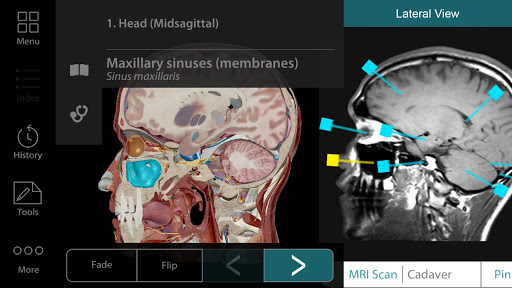

More detailed gross anatomy

The male and female gross anatomy models have over a hundred new refinements!

Additional nerves, arteries, and veins in the head and neck region.

New 3D brain anatomy: Refined model of the cerebrum, new motor and sensory maps, and new dermatomes.

Tag structures! Use the new 3D labels feature to show the name of multiple structures on screen.

* New 3D Gross Anatomy Lab! Dissect a virtual cadaver in the prone or supine position.